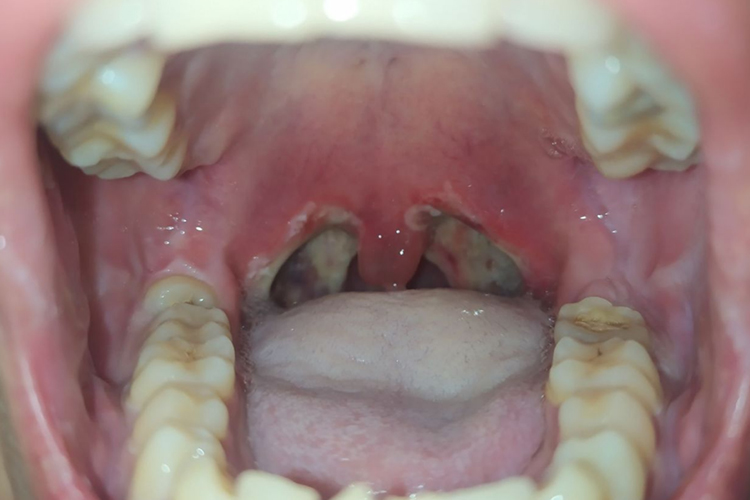

扁桃体摘除术后6小时伤口即有白膜形成,术后第二天扁桃体窝已完全覆盖白膜,术后10天内逐渐脱落。大概半个月可以完全脱落,伤口逐渐恢复。